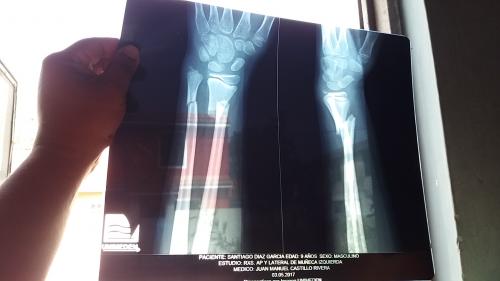

El pequeño Santiago, de tan solo nueve años y quien vive en la colonia ferrocarrilera, tuvo una seria lesión en su brazo, por lo que requiere de una operación que tiene un costo de 12 mil pesos, ya que se le deberán colocar 4 clavos en el brazo para que sane la lesión de manera correcta.

La madre del menor, señaló que llevó a su hijo a un médico particular, esto al no contar con seguridad social, por lo que tuvieron que tomarle una radiografía al niño, detectando la doble fractura en su brazo izquierdo.